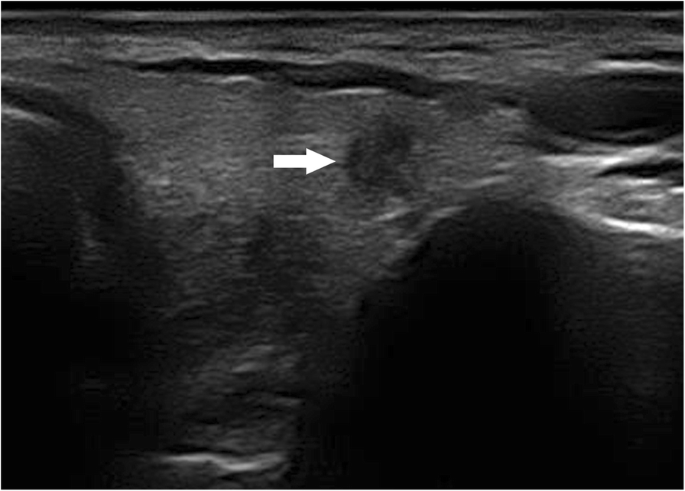

The results of the multivariate logistic regression analysis for US characteristics are summarized in Table 3. The proportion of MTMCs with ovoid to round shapes (Figs. 1 and 2) was higher than that of PTMCs (Fig. 3) (54.35% vs 9.56%, P = 0.007), but PTMCs with taller-than-wide shapes (Figs. 4 and 5) were much more common than MTMCs with the same shape (Fig. 6) (59.56% vs 19.57%, P = 0.000). An unclear boundary seemed to be more commonly detected in PTMCs (Fig. 3) than in MTMCs; however, there was no significant difference (86.03% vs 43.48%, P = 0.188). There were more nodules with a > 50% solid composition in the MTMC group than in the PTMC group (13.04% vs 1.47%, P = 0.032). Calcifications were not commonly observed in either group; when they occurred, macrocalcifications were more often seen in MTMCs (Fig. 2) than in PTMCs (Fig. 3) (21.74% vs 6.62%, P = 0.004). Microcalcifications were more frequently detected in PTMCs (Fig. 4), although there was no significant difference (10.87% vs 29.41%, P = 0.214). Hypervascularity was observed in 58.70% of MTMCs but only in 19.85% of PTMCs (P = 0.000).

PTC usually has highly intense fibrosis, and its compressibility is reduced, resulting in its upright morphology [17]. A taller-than-wide shape has been regarded as an ultrasonographic feature of PTMCs [18, 19]. In our study, this was also a common sign in the PTMC group, and the proportion of PTMCs with this sign was as high as 59.56%. However, there were only 9 (19.57%) tumors with a taller-than-wide shape in the MTMC group, which indicated that this sign did not apply to MTMCs. Previous studies have shown that, regardless of size, MTCs were mostly round or ovoid in shape rather than taller-than-wide [20, 21]. Similar results were also observed in our series. The MTMC nodules were more likely to be ovoid to round than PTMCs, and the difference was statistically significant (P = 0.000).